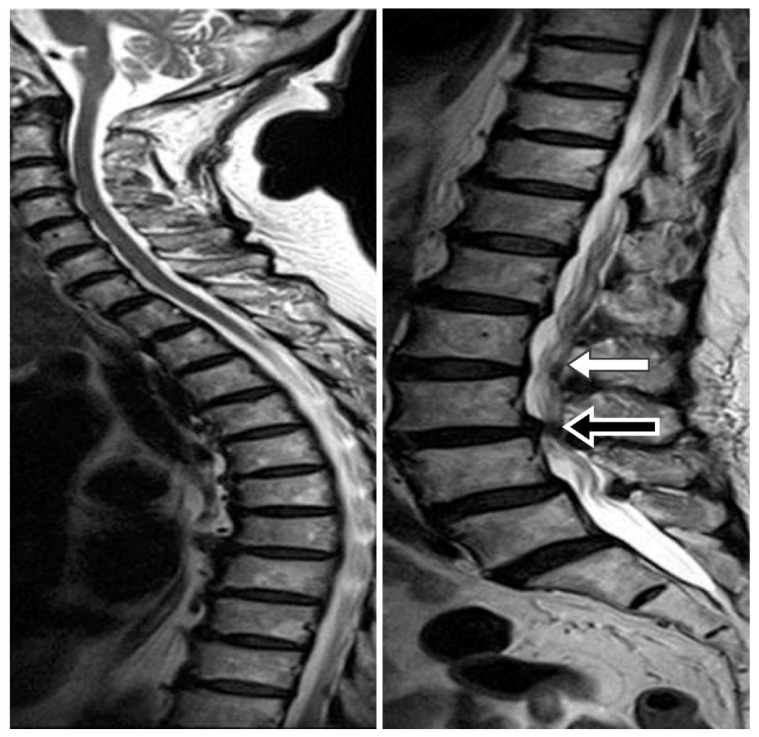

Brain MRI or CT was performed to confirm the hydrocephalus diagnosis. A whole spinal series MRI was also performed to confirm the patency of the spinal canal. We were able to identify a severe stenosis of the spinal canal or a spinal tumor that might block the patency of the CSF from the ventricle to LP shunt. The spine MRI was used to facilitate carrying out the tapping step while avoiding the stenosis segment (Figure 1). We used Medtronic Strata® NSC LP adjustable pressure shunts for all patients and these were initially set at the highest pressure (pressure: 2.5, 20 cm H2O).

This whole spine MRI showing that we could carry out the tapping step while avoiding the stenosis segment. Taking this case as an example, severe stenosis was noted at L3–4 (black arrow) level, and we were able to perform the puncture easily from L2–3 (white arrow).